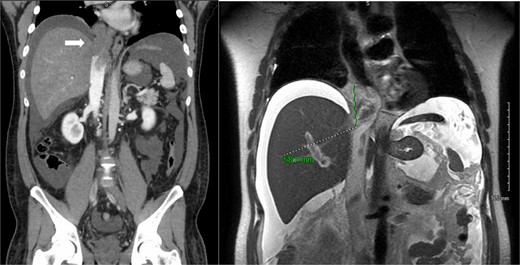

A 36-year-old male with no significant medical history presented with a 10-day history of fatigue, abdominal bloating, bilateral lower extremity edema, and 20 lbs weight gain. Computed tomography (CT) scan of his abdomen revealed a 5-cm lobulated mass within the infra- and suprahepatic IVC extending into the right atrium. Magnetic resonance imaging (MRI) showed that the mass likely originated from the suprahepatic IVC and extended into both the infrahepatic IVC and right atrium (Fig. 1). A transfemoral biopsy diagnosed a poorly differentiated, monophasic synovial sarcoma. He was medically managed and discharged on hospital Day 4. An outpatient positron emission tomography CT failed to show evidence of metastatic disease. The case was discussed in a multidisciplinary conference, and the patient was thought to be a good surgical candidate.

Primary IVC synovial sarcoma extending from the retrohepatic cava into the right atrium. Left: coronal slice of abdominal CT scan with IV contrast showing occlusive intravascular lesion (white arrow). Right: coronal abdominal MRI T2 slice demonstrating 5.8 cm enhancing intravascular lesion.